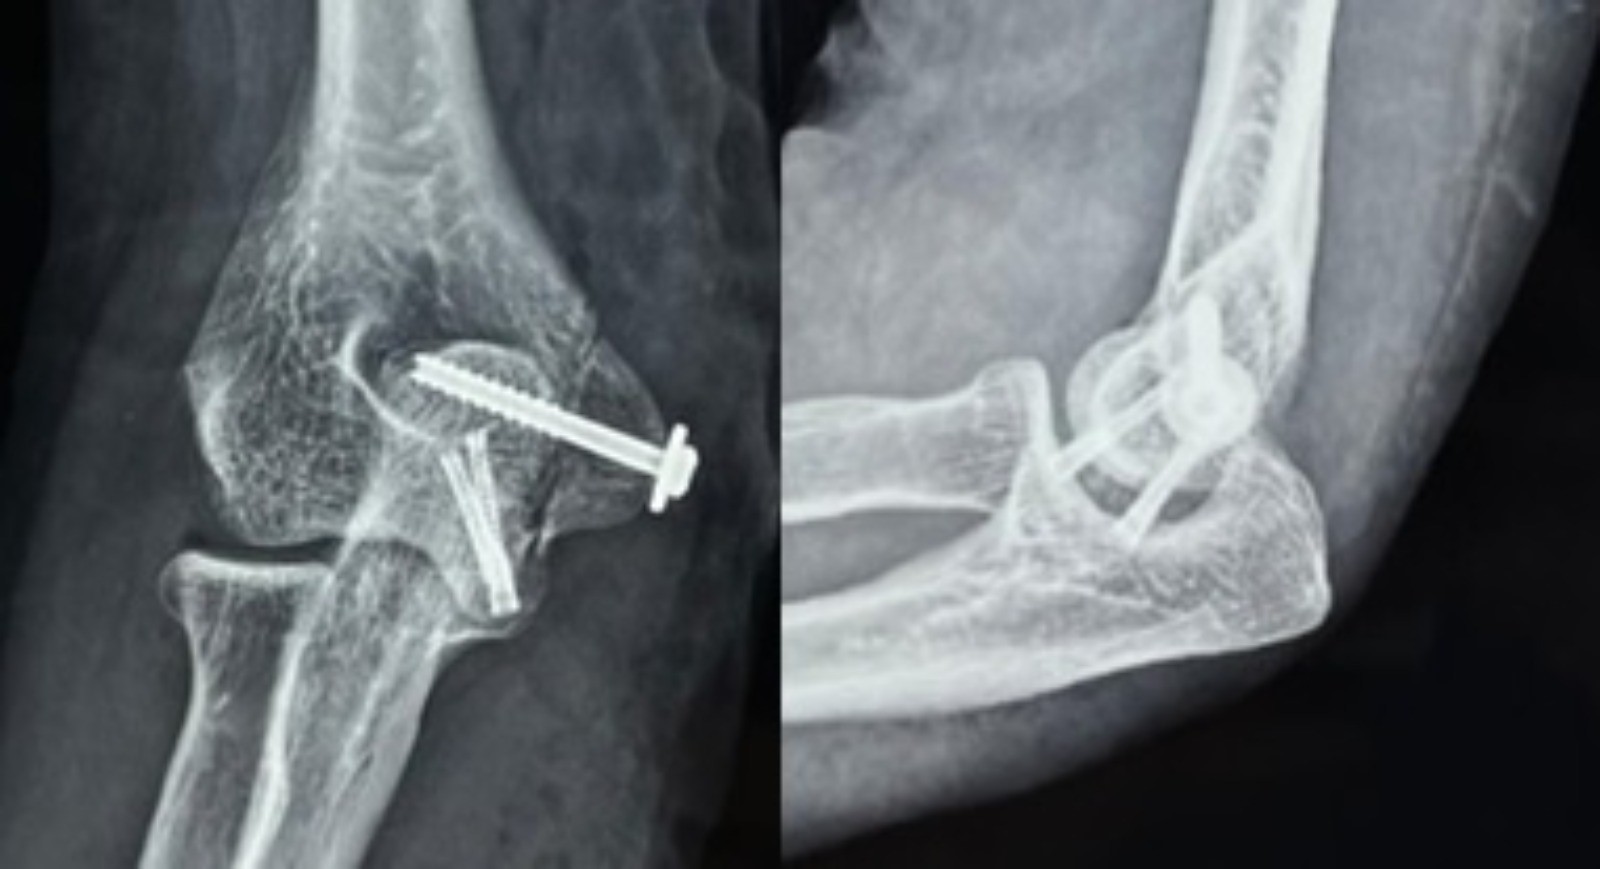

The patient was planned for open fixation of the fracture to maintain articular congruency and provide an acceptable range for her limb. A standard medial approach to the elbow was taken. The plane was developed between the brachialis and triceps proximally and the pronator teres and brachialis distally after isolating the ulnar nerve (Fig. 3). Given the difficulty in accessing the fracture fragment, which was positioned anterior to the medial condyle, an osteotomy of the medial epicondyle was performed, preserving the common flexor origin (Fig. 4). The capsule was dissected, preserving the medial collateral ligament (MCL) to expose the articular surface. The large osteochondral fragment of the trochlea of size 2.4 cm × 1.2 cm was found displaced anterosuperiorly without significant loss of articular cartilage (Fig. 5). Fracture margins were freshened, and anatomy was delineated. Two titanium 3.3 mm variable pitch headless screws were used to fix the fracture fragment to the trochlear bed from directions inferomedial to superolateral, carefully measuring the depth and direction of screw insertion to avoid penetrating the olecranon fossa using image guidance. Articular congruency was achieved (Fig. 6 and 7). The medial epicondyle osteotomy was fixed with standard cannulated 4 mm partially threaded cancellous screws with a washer, preserving the common flexor origin, and the joint capsule was closed. The elbow range was checked under fluoroscopy and found satisfactory. Medial approach closure was done.

Figure 7: Post-operative radiographs showing anatomically reduced trochlear fragment with a congruent ulnohumeral articulation.